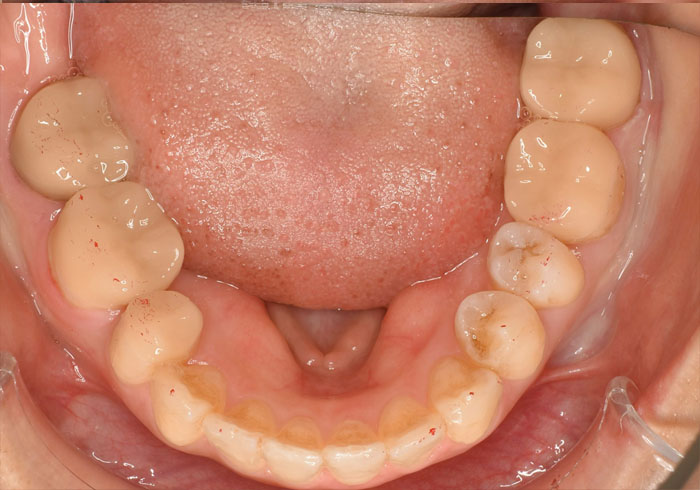

治療後

マウスピース矯正 マウスピース矯正 マウスピース矯正

もともと右上前から4番目の歯が1本欠損しており、左右のバランスを合わせるために右下の歯を1本抜歯して治療を行いました。

必ずしも歯を抜かないと矯正治療ができないというわけではありませんが「笑顔やお顔とのバランス」を考慮し、今回は抜歯を提案させていただきました。